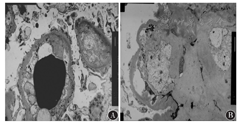

本科阅读外院肾脏穿刺病理切片结果示:光镜下可见27个肾小球,其中2个小球全球硬化,余小球呈弥漫性重度系膜增生,系膜基质明显增多呈结节状,毛细血管腔受压明显狭窄,脏层及壁层上皮肿胀。肾小管上皮颗粒变性,灶状萎缩,肾间质灶状淋巴、单核细胞浸润伴纤维化。部分小叶间动脉、入球小动脉及出球小动脉见玻璃样变。PAS(+),PASM(+),Masson(+),刚果红染色(-)。见图1。免疫荧光为IgG(2+),沿毛细血管壁线状沉积;C3(+)。见图2。电镜见肾小球系膜细胞和基质明显增生,基底膜轻度增厚,系膜区及基底膜内未见异常电子致密物沉积,上皮足突大部分融合,肾小管上皮溶酶体增多。见图3。

注:A:PAS染色;B:PASM染色;C:Masson染色